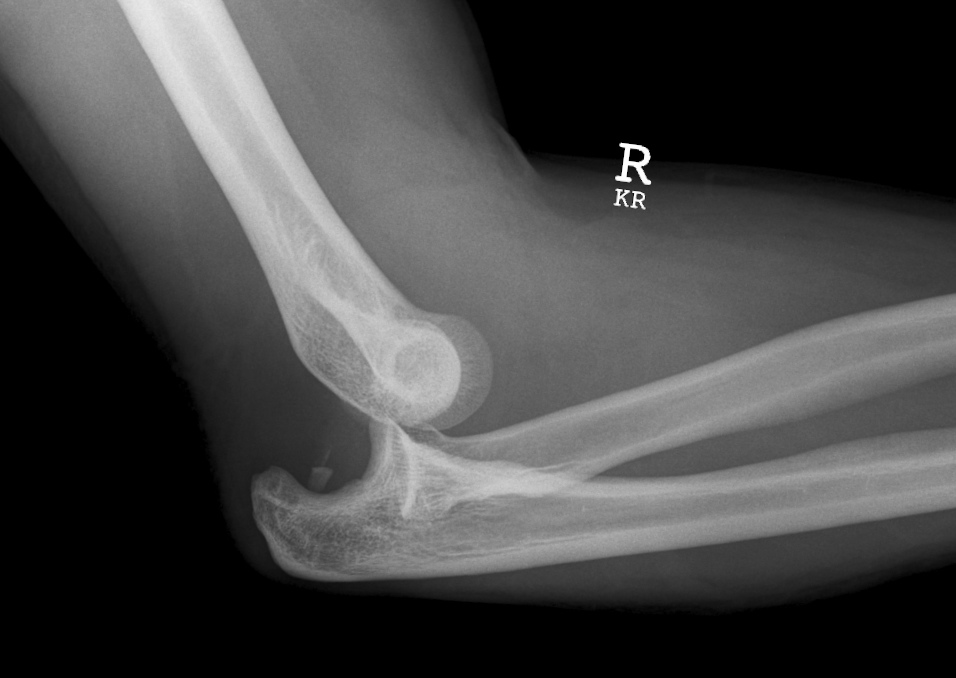

вот так выглядит вывих локтевого сустава. а еще вывих сопровождается ограничением движений в суставе. но вывихи встречаются относительно нечасто

Моё любимое в работе - просмотр рентгенограмм. В условиях травмпункта нет возможности выполнить КТ или МРТ, поэтому повреждения мягких тканей диагностируют по результатам осмотра, а при подозрении на перелом или вывих - отправляют на рентген. Ждать описания рентгенолога возможности нет, особенно ночью, поэтому врачу необходимо смотреть самостоятельно и выносить вердикт.